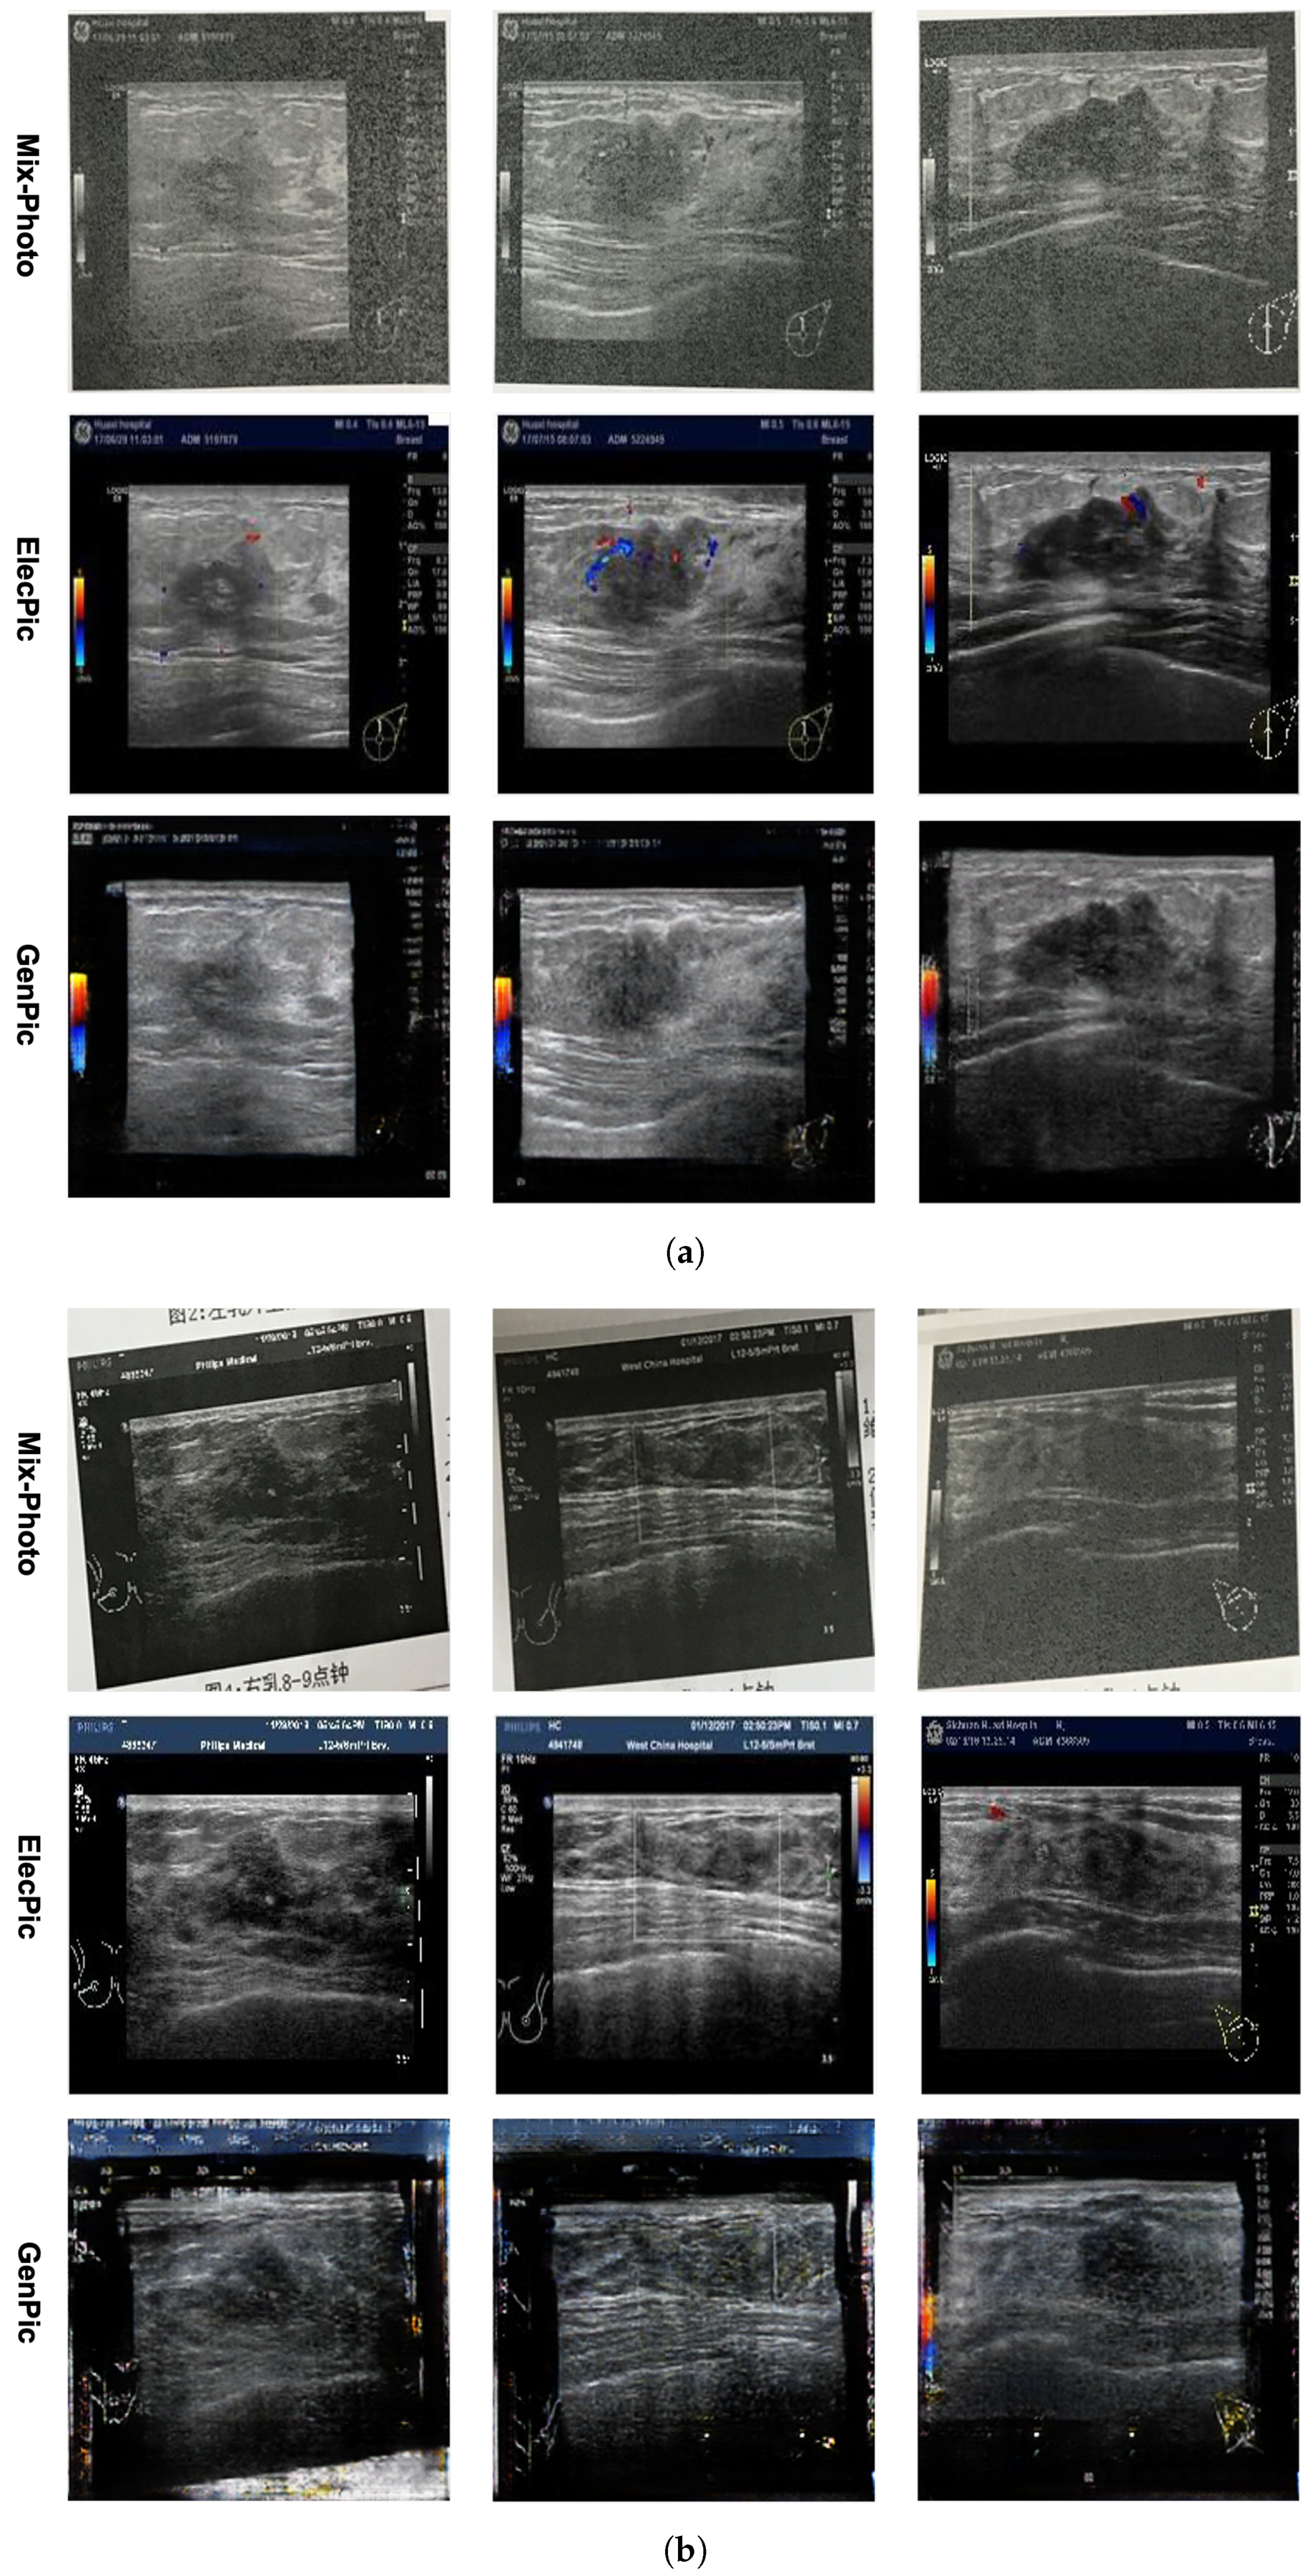

4.1.3. Generative Model

The generative model is trained using the Mix-Photo and ElecPic datasets, mainly to remove noises such as deformation, glare and rotation in the Mix-Photo dataset. The generated images are called GenPic. The generative model used in this article removes image noises, as shown in Figure 3.

From Figure 3a, it can be seen that the generative model has a strong ability to remove light spot noise, and the generated images are very close to the ElecPic images. It also removes the color flow Doppler on the ElecPic images, making the tumor area more prominent. It can be seen from Figure 3b that the generative model cannot handle images with significant deformation noise very well. The deformation of Mix-Photo in the first column is more significant, resulting in a significant difference between the GenPic and ElecPic. The images in the second and third columns have less deformation, and GenPic is closer to ElecPic. In addition to light spot and deformation noises, there is also significant rotation. We use the proposed rotation classification model to remove this noise, and the image generation results can be viewed in the comparison shown in Figure 4. In addition to the subjective analysis of GenPic, we also compared the performance differences of the breast ultrasound report classification model when inputting GenPic and Mix-Photo. For details, please refer to Section 4.3.4 of this article for comparative experiments.

Figure 3. Noise removal performance of generative model on breast ultrasound photos. (a) Image comparison with light spot noise. (b) Image comparison with deformation noise.